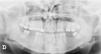

A 27-year-old female patient presented with a six-month history of a persistent and painful nodule on the chin. She referred occasional purulent exudate. There was no history of fever or systemic symptoms. Several courses of oral antibiotics had been ineffective. In the extraoral examination she presented an erythematous nodule with an important surrounding retraction (Fig. 1). Ultrasonography (Esaote MyLab Gamma®, 18 MHz) revealed a hypoechoic lesion with increased blood flow in the base and periphery. Moreover, an inflamed tortuous sinus tract extended through the subcutaneous tissue to the alveolar bone (Fig. 2). These findings were consistent with an odontogenic cutaneous fistula (OCF). A panoramic radiograph showed its origin in a mandibular incisor (Fig. 3). The patient was referred to the Maxillofacial Surgery Department of this hospital for assessment and treatment. Dental extraction was suggested in order to remove the source of the infection.

The diagnosis of OCF is usually made based on panoramic radiograph and computed tomography that show the damage of the alveolar process. However, these tests require considerable time and money to perform and may have side effects. Skin ultrasonography is a noninvasive and emerging technique with proven usefulness in localized lesions.3 High frequency imaging not only provides robust qualitative and quantitative information on skin lesions but also on their surrounding tissues. Moreover, color Doppler ultrasonography gives information about its vascularization. Therefore, this technique has been found really useful in the diagnosis of cutaneous sinus tracts. Ultrasound image of OCF consists of a hypoechoic linear but slightly tortuous sinus tract that reaches the cortical bone, with an increased blood flow in the peripheral regions of the tract.4,5 Most of these features characterize this lesion and easily distinguish it from other pathologies included in the clinical differential diagnosis. Regarding its treatment, antibiotic therapy brings an apparent healing, but if the source of infection is not eliminated, the sinus tract recurs in time. It is believed that high-frequency ultrasonography could also be useful in monitoring response to treatment by showing a decrease in the vascularization and a progressive reduction of the sinus tract. In addition, it could also allow the detection of early recurrences. In order to accomplish resolution, therapy has to focus towards the management of the dental infection, either with endodontic treatment or extraction.2 Surgical excision of the sinus tract is not usually necessary, as it heals spontaneously after the dental treatment.